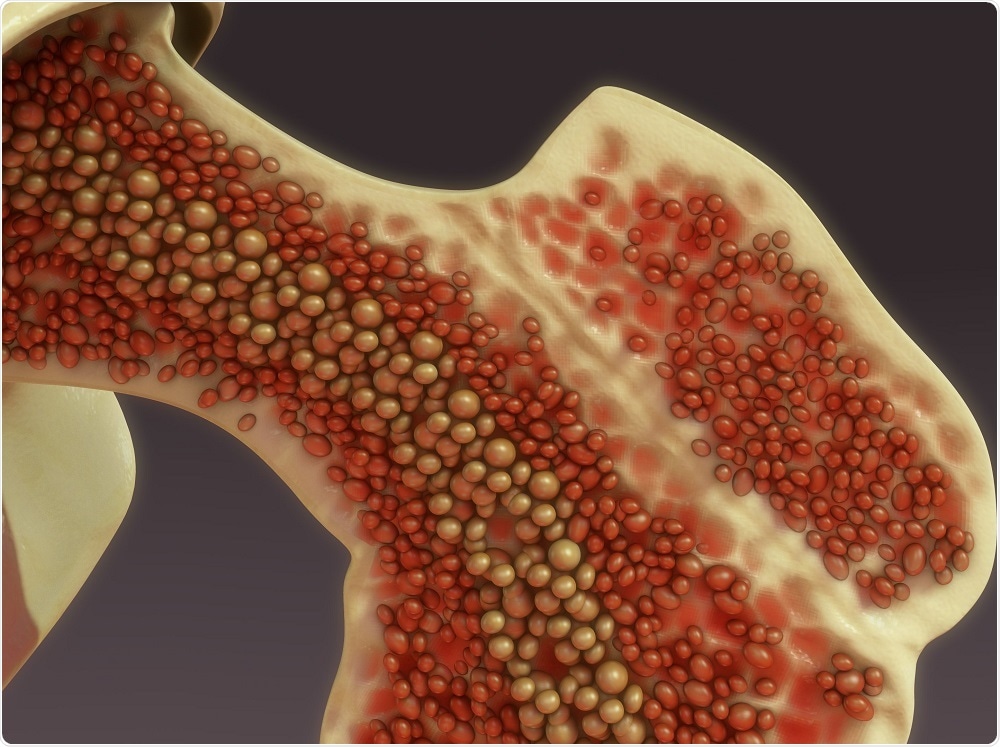

Genellikle kemikler yapısal olarak sağlam, özellikle de sert dış tabakası bulunan kortikal kemik olarak düşünülür. Ancak hem hayvanlarda hem de insanlarda bu katı kısmı geçen daha önce hiç görülmemiş gizli geçitler keşfedildi. Bu keşif sonrası temel iskelet anatomisi ve işlevinin yeniden düşünülmesi gerekebilir. Yeni yapılan bir çalışmada Almanya’daki araştırmacılar, kemik içinde gizli bir tünel sistemi gibi davranan, kan ve bağışıklık hücrelerinin vücutta etkin ve hızlı bir şekilde yayılmasına yardımcı olan daha önce tespit edilmemiş bir ince kan damarı ağı bulduklarını bildirdi.

Duisburg-Essen Üniversitesi’nden moleküler immünologMatthiasGunzer, ‘Bu 21. yüzyılda basılmış herhangi kitapta tarif edilmemiş yeni ve merkezi anatomik yapı. Bunu bulabileceğimizi gerçekten hiç beklemiyorduk’ açıklamasını yaptı. Trans-kortikal damarlar’ (TCV’ler) olarak adlandırılan bu küçük kanallar bilim için yeni olabilir, ancak savaş alanına ilk giren acil ilaç infüzyonlarının yaralı askerleri hızla nasıl canlandırabildiklerini açıklamaya yardımcı oluyorlar.Bu gibi acil durumlarda, sağlık görevlilerinin damarları bulması ve bunlara erişmesi gerekiyor. Sağlık görevlilerinin doğrudan kemik iliğine ilaç enjekte etme yoluna gitme zamanları ve yetenekleri yok.  Yeni araştırmaya ilişkin bir yorumda, ‘Kemikte karmaşık bir kan sisteminin varlığına dair kanıtlar oluşmasına rağmen, hücrelerin ve sıvının kemik iliğinden dolaşıma doğru girebilmesinisağlayan moleküler mekanizmalar ve anatomi, belirsiz kalmıştır” diye açıklıyor. Şimdi, bu mekanizmanın temeli ilk defa birkaç yıl önce kaza ile tespit edildi. Bir çalışma için Gunzer, farelerde flüoresanla boyanmış kan hücreleri inceliyordu ve bunların katı kemiğin içinden geçmesi mikroskop altında gözlemledi. Tıbbi literatürde fenomeni açıklayabilecek hiçbir şey bulunmuyor.

Kesinlikle diğer laboratuvarlarda bazı replikasyonlara ihtiyaç duyacak’ dedi. Ekip, bir insan gönüllünün bacak kemiğini (Gunzer’in kendisi) görüntüleyerek insan anatomisini incelediğinde, daha kalın olmalarına rağmen aynı tür TCV yapılarının kanıtlarını buldular ve araştırmacılar tam işlevlerini doğrulamak için daha fazla çalışmanın gerekli olduğunu kabul ettiler. Bu gizli geçitlerin bugüne dek nasıl fark edilmediğine gelince ekip, keşfin görüntüleme konusunda teknolojik gelişmelere bağlı olduğunu, ancak yine de bu beklenmedik keşifle şaşırdıklarını söylüyor. Gunzer, “İnsan anatomisi hakkında hala öğrenilecek şeyler var. Kan damarlarını daha önce bilmediğimiz yeni bir yerde keşfettik’ dedi. Geçen yıl Harvard liderliğindeki bir çalışmanın ortaya çıkardığı kafatasındaki başka bir gizli tünel sistemini hatırlatan keşif, iltihaplı hastalıklar, doku yaralanmaları, hücre göçü veya kanın nasıl aktığını anlamak için her türlü yeni tıbbi ipucunu ortaya çıkarabilir.